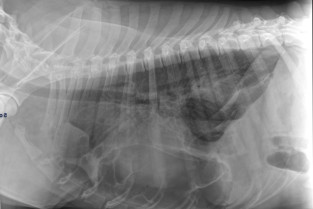

Cette première journée est consacrée à la sémiologie respiratoire, aux affections naso-sinusales, laryngées, pharyngées et de l’espace pleural.

- maitriser la démarche diagnostique face à un épanchement pleural liquidien et la conduite thérapeutique lors de chylothorax et de pyothorax.